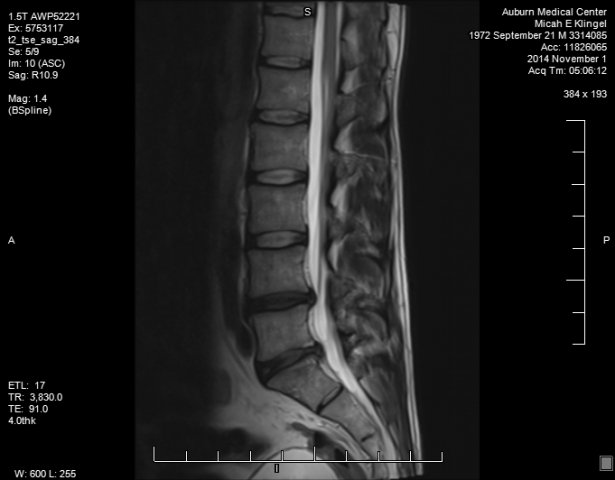

280zex Posted December 6, 2014 Author Share Posted December 6, 2014 Actualy i picthed everybody involved as much hell as i could throw at them. 9drs, 3 chiro, 2 phys theripst, L and i too. Nobody listened until a friend hooked me up with the highest ranked neurosurgon in the PNW. He took 1 look at my mri and said congrats you broke your back, you need emergency surgery-now. Im gona scrub up, call who you need to, my people will be in here in 15min to prep ya. The dr did this for free, he new i was in trouble- big trouble. I will also be getting free legal assistance, gona go after the jerky dr who said i was fine, and the dept of L and i for failure of due process. My company fired me for failure to show up for work. How can i show up for work if im getting major lower back surgery!!!! Dont ever trust what 1 dr tells you, get other opinions, and if they dont seem right- keep looking!!!!!! I walked around for damn near 3 months with a broken back, and had to fight for my own health. I refuse to go down without a fight, ever. The best part is i have been dealing with this with NO pain killers, keeps me motivated. I just got home from surgery, cant wait until monday to talk with lawyer. This gona be fun!!!! Quote Link to comment Share on other sites More sharing options...

280zex Posted December 7, 2014 Author Share Posted December 7, 2014 no fused bone and what not. the dr and I have a plan A/plan B thing. plan A involved removing some disc material, some bone off the vertebra, and repairing part of a broken framen. if plan A doesnt work, then there is the ugly plan B. I dont want to even think about that!!! I did get a lawyer, and she was like a child in a candy store when I explained what was going on. my whole case was mis-handled and I have all the proof in paper and electronic communication. I can at least feel my feet again, so thats a good thing. I'm just going to assume this legal mumbo jumbo is going to take quite some time. Quote Link to comment Share on other sites More sharing options...